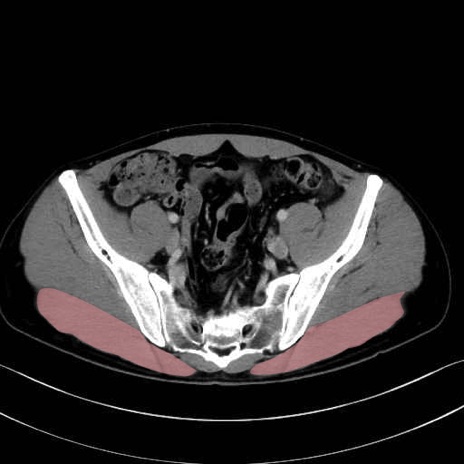

3. 殿部の筋肉(表層・中層・深層)

大殿筋 (Gluteus maximus)